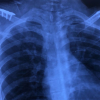

Standard antero-posterior, Grashey and lateral view radiographs were taken both pre- and post-operatively. A pre-operative computed tomography (CT) scan with 3D reconstruction was obtained in all patients for accurate assessment of fracture configuration and measurements of parameters of displacement. The orthopedic trauma association/arbeitsgemeinschaft fur osteosynthesefragen classification system was used to classify both clavicle and scapula. Patients eligible for the study were skeletally mature patients >18 years of age, fresh (injuries within 14 days of presentation) double disruption of the SSSC which met the criteria for significant displacement. Exclusion criteria included minimally displaced floating shoulder, associated neurovascular injury, previously operated shoulder, previous malunion and/or nonunion. Operative indications for ipsilateral fractures comprised of GPA <20°, medialization of >25 mm, open fractures, clavicular shortening of >20 mm or displacement >10 mm with no cortical contact/comminution. Distances and angles were calculated using picture archiving and communication system or by manual methods using protractors. The GPA is measured on 3D CT reconstruction by the angle created by two lines- line 1 extending from the superior glenoid pole to inferior glenoid pole and line 2 connecting the superior glenoid pole to the inferior most pole of inferior pole of scapula. Medialization/lateralization displacement is measured similarly by determining the distance between the vertical planes drawn at the lateral most edge of both scapular fragments (Fig. 1). All patients were operated in floppy lateral decubitus with shoulder girdle and the whole upper limb prepared and draped. Clavicle fracture was fixed first in all cases with an anatomical 3.5 mm clavicle plate using standard direct approach. Brodsky’s direct lateral column approach was taken to fix the scapula which utilizes the plane between infraspinatus and teres minor. 3.5 reconstruction plates, molded to match anatomy, were used for fixing the lateral pillar. Reduction and fixation of clavicle first allows for ease of reduction of the scapular segment; both fixations were carried out in the same seating (Fig. 2 and 3). The shoulder was kept in a universal shoulder immobilizer for up to one week depending upon the associated injuries, following which gentle pendulum exercises with passive movements for the shoulder girdle were initiated. Full range of movements compatible with activities of daily living was started at 2 months. Patients were evaluated clinically with Herscovici and American shoulder and Elbow score (ASES) scoring system and imaged at regular intervals of 2, 6 and 12 weeks in AP, lateral, Grashey views. Additional follow-up for any complication including but not limited to plate prominence, poor range of motion, persistent pain for a period of 18 months (Fig. 4).

The mean time for signs of radiological union to be seen in clavicle was 13.55 weeks and for scapula it was seen to be 8.5 weeks. Cases with blunt trauma chest presented with hemothorax and/or pneumothorax were managed with an intercostal drain insertion for 5 days till breath sounds were equal bilaterally. Patients with head injury who had multiple hemorrhagic contusions on CT Head; was managed conservatively. No patient in our series had head injury which warranted surgery.